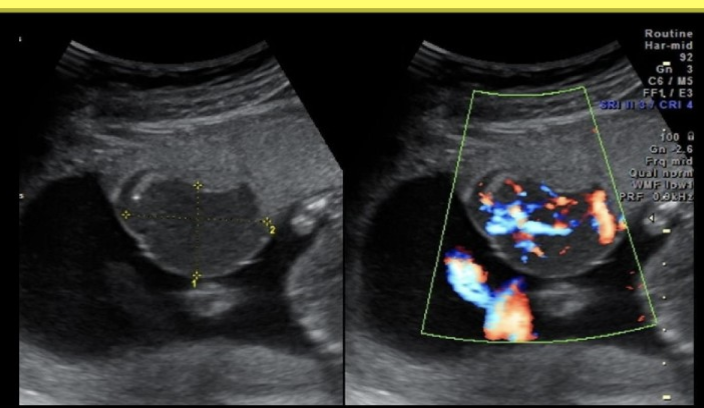

while scanning the fetal heart in the 4 chamber view,

.

.you identify an echogenic focus near the apex of the left ventricle + two more along the ventricular septum.

these would cause the greatest increase in suspicion for what fetal syndrome

a) trisomy 21

b) trisomy 18

c) trisomy 13

d) turner syndrome